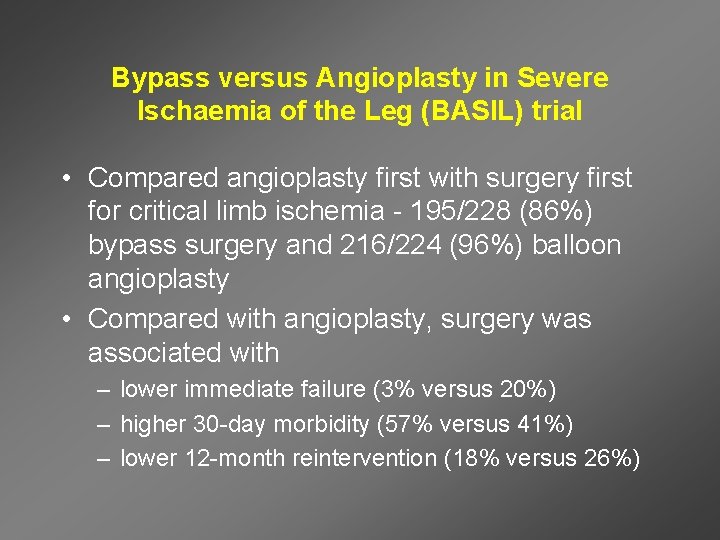

Bypass versus Angioplasty in Severe Ischaemia of the Leg (BASIL) trial • Compared angioplasty first with surgery first for critical limb ischemia - 195/228 (86%) bypass surgery and 216/224 (96%) balloon angioplasty • Compared with angioplasty, surgery was associated with – lower immediate failure (3% versus 20%) – higher 30 -day morbidity (57% versus 41%) – lower 12 -month reintervention (18% versus 26%)